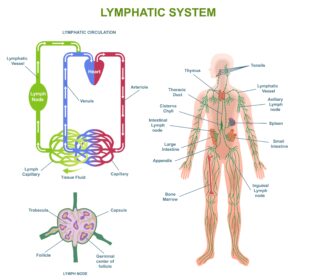

Hodžkino limfoma – tai vėžys, kuris prasideda limfinėje sistemoje. Ši liga gana retai pasitaiko, bet dažniausiai diagnozuojama jauniems žmonėms. Ankstyvas atpažinimas ir ...